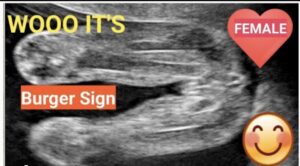

بينما تظهر اعضاء الاجنة الإناث في شكل ثلاثة خطوط متوازية ويسمى هذا الشكل علامة البرجر (كأن الثلاثة خطوط هم شطيرتي الخبز بينهما البرجر) كما يتضح في هذه الصورة.